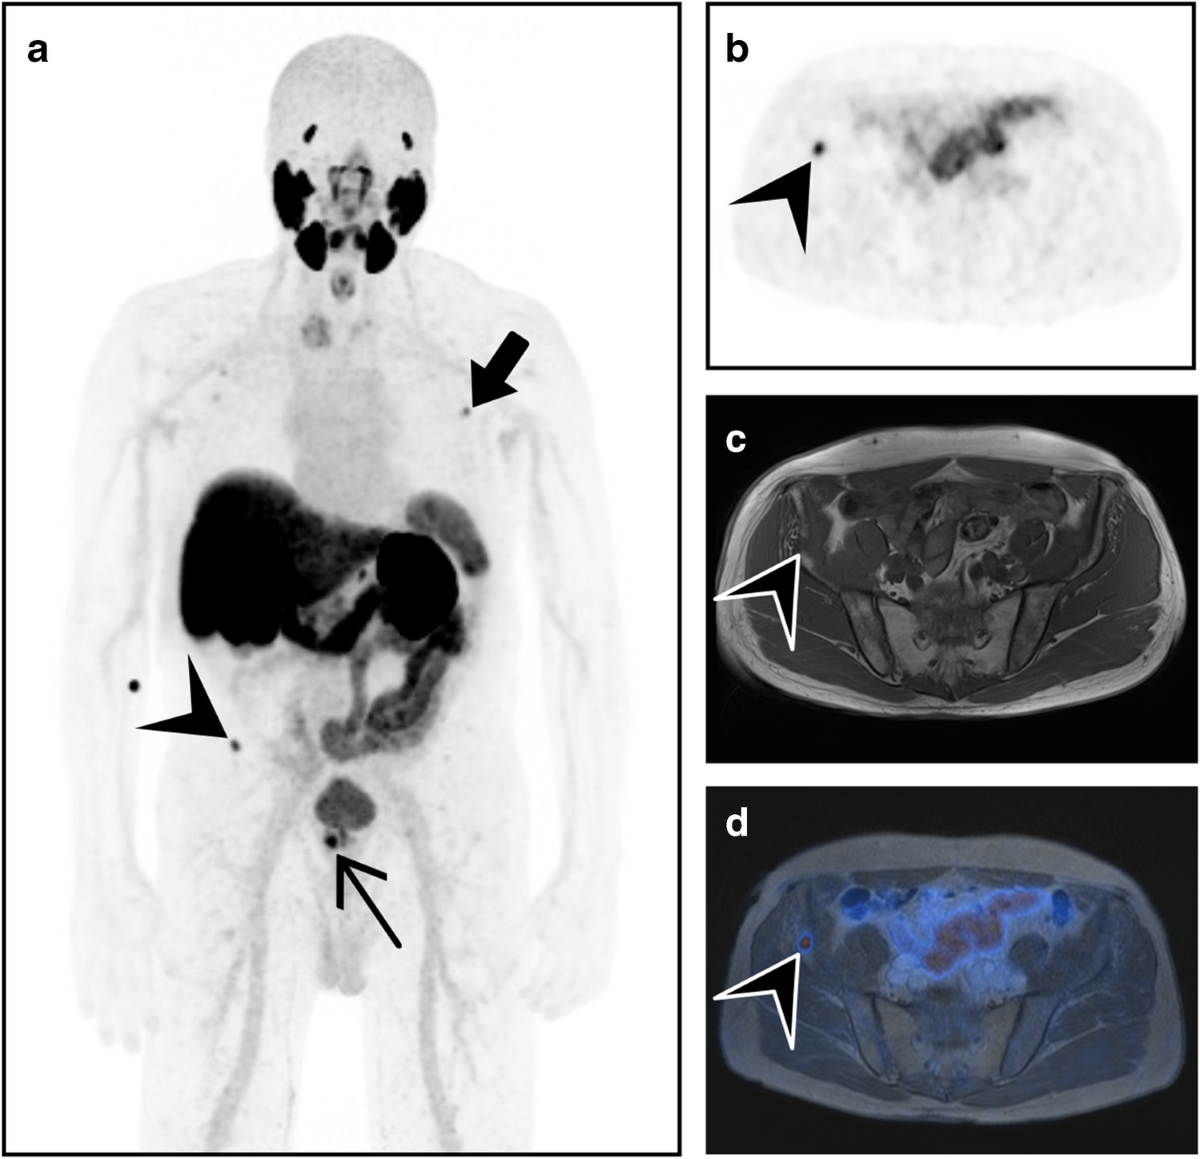

Frontiers | Which Way to Choose for the Treatment of Metastatic Prostate Cancer: A Case Report and Literature Review

image size: 1772x1772